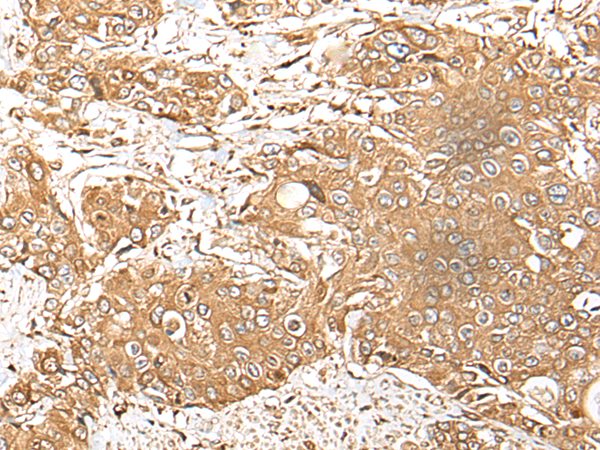

分类: 科研抗体货号: P02407别名: hSAD1应用: IHC反应种属: Human, Mouse, Rat